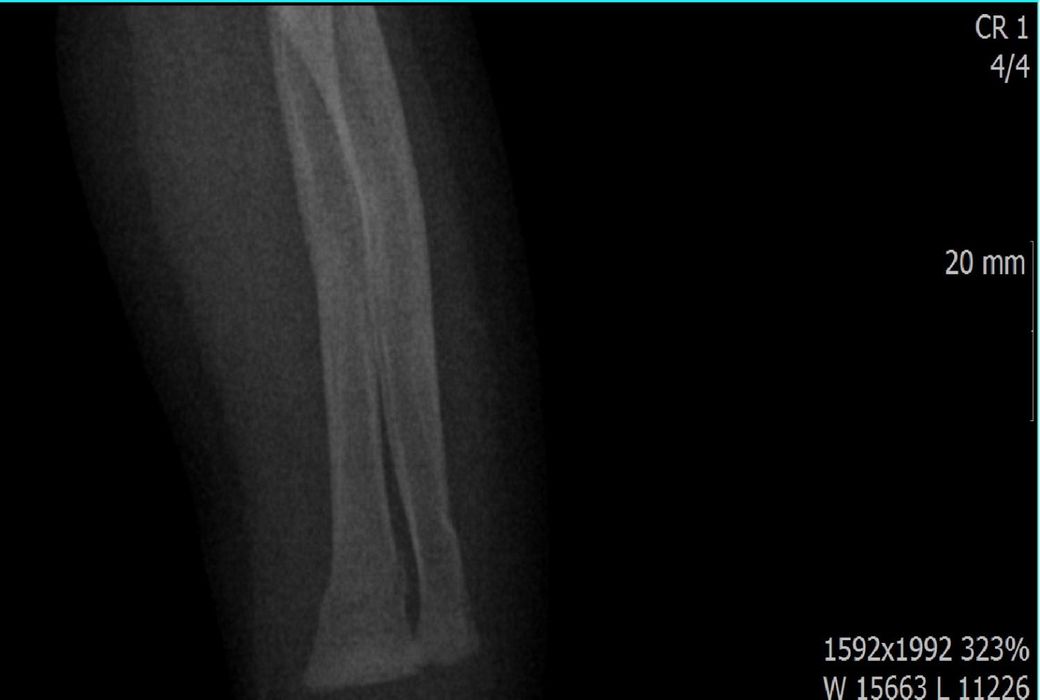

다름이 아니라, 첨부드린 엑스레이(X-ray) 사진처럼 골절 사실을 알게 되고 골절 발생 시점 대략적으로나마 추정시기를 파악하려고 문의 드리게 되었습니다

1) 3월 30일 촬영한 X-ray만으로 정확한 골절 시기를 100% 특정하는 데에는 한계가 있다는 점 충분히 인지하고 있기에 촬영날짜 기준으로 대략적으로 어느정도 시점에서 발생되었을 것으로 추측(ex 당일, 7~10일전, 7~14일 전, 10일 ~ 20일전, 14일 ~ 30일전 등등등)되는지 이해하고 싶습니다.

• 1번 째 사진

하지만, 아예 불가능한건 아니고 골절선이 얼마나 뚜렷하냐, 골막 반응이 보이느냐, 연골성 가골 형성이 있느냐 등으로 골절 시기를 추정해볼 수 있습니다.

골절선이 뚜렷하면 0~1주, 골막 반응이 시작되면 1~2주, 연골성 가골이 형성되기 시작하면 2~3주, 가골이 명확해지면 3~6주 정도로 추정할 수 있습니다.

골절선이 흐려졌고 가골이 형성되기 시작하는 2~3주경이 아닌가 의심이 되지만 제가 골절을 주로 보는 정형외과 전문의가 아니라서 정확도가 떨어집니다.